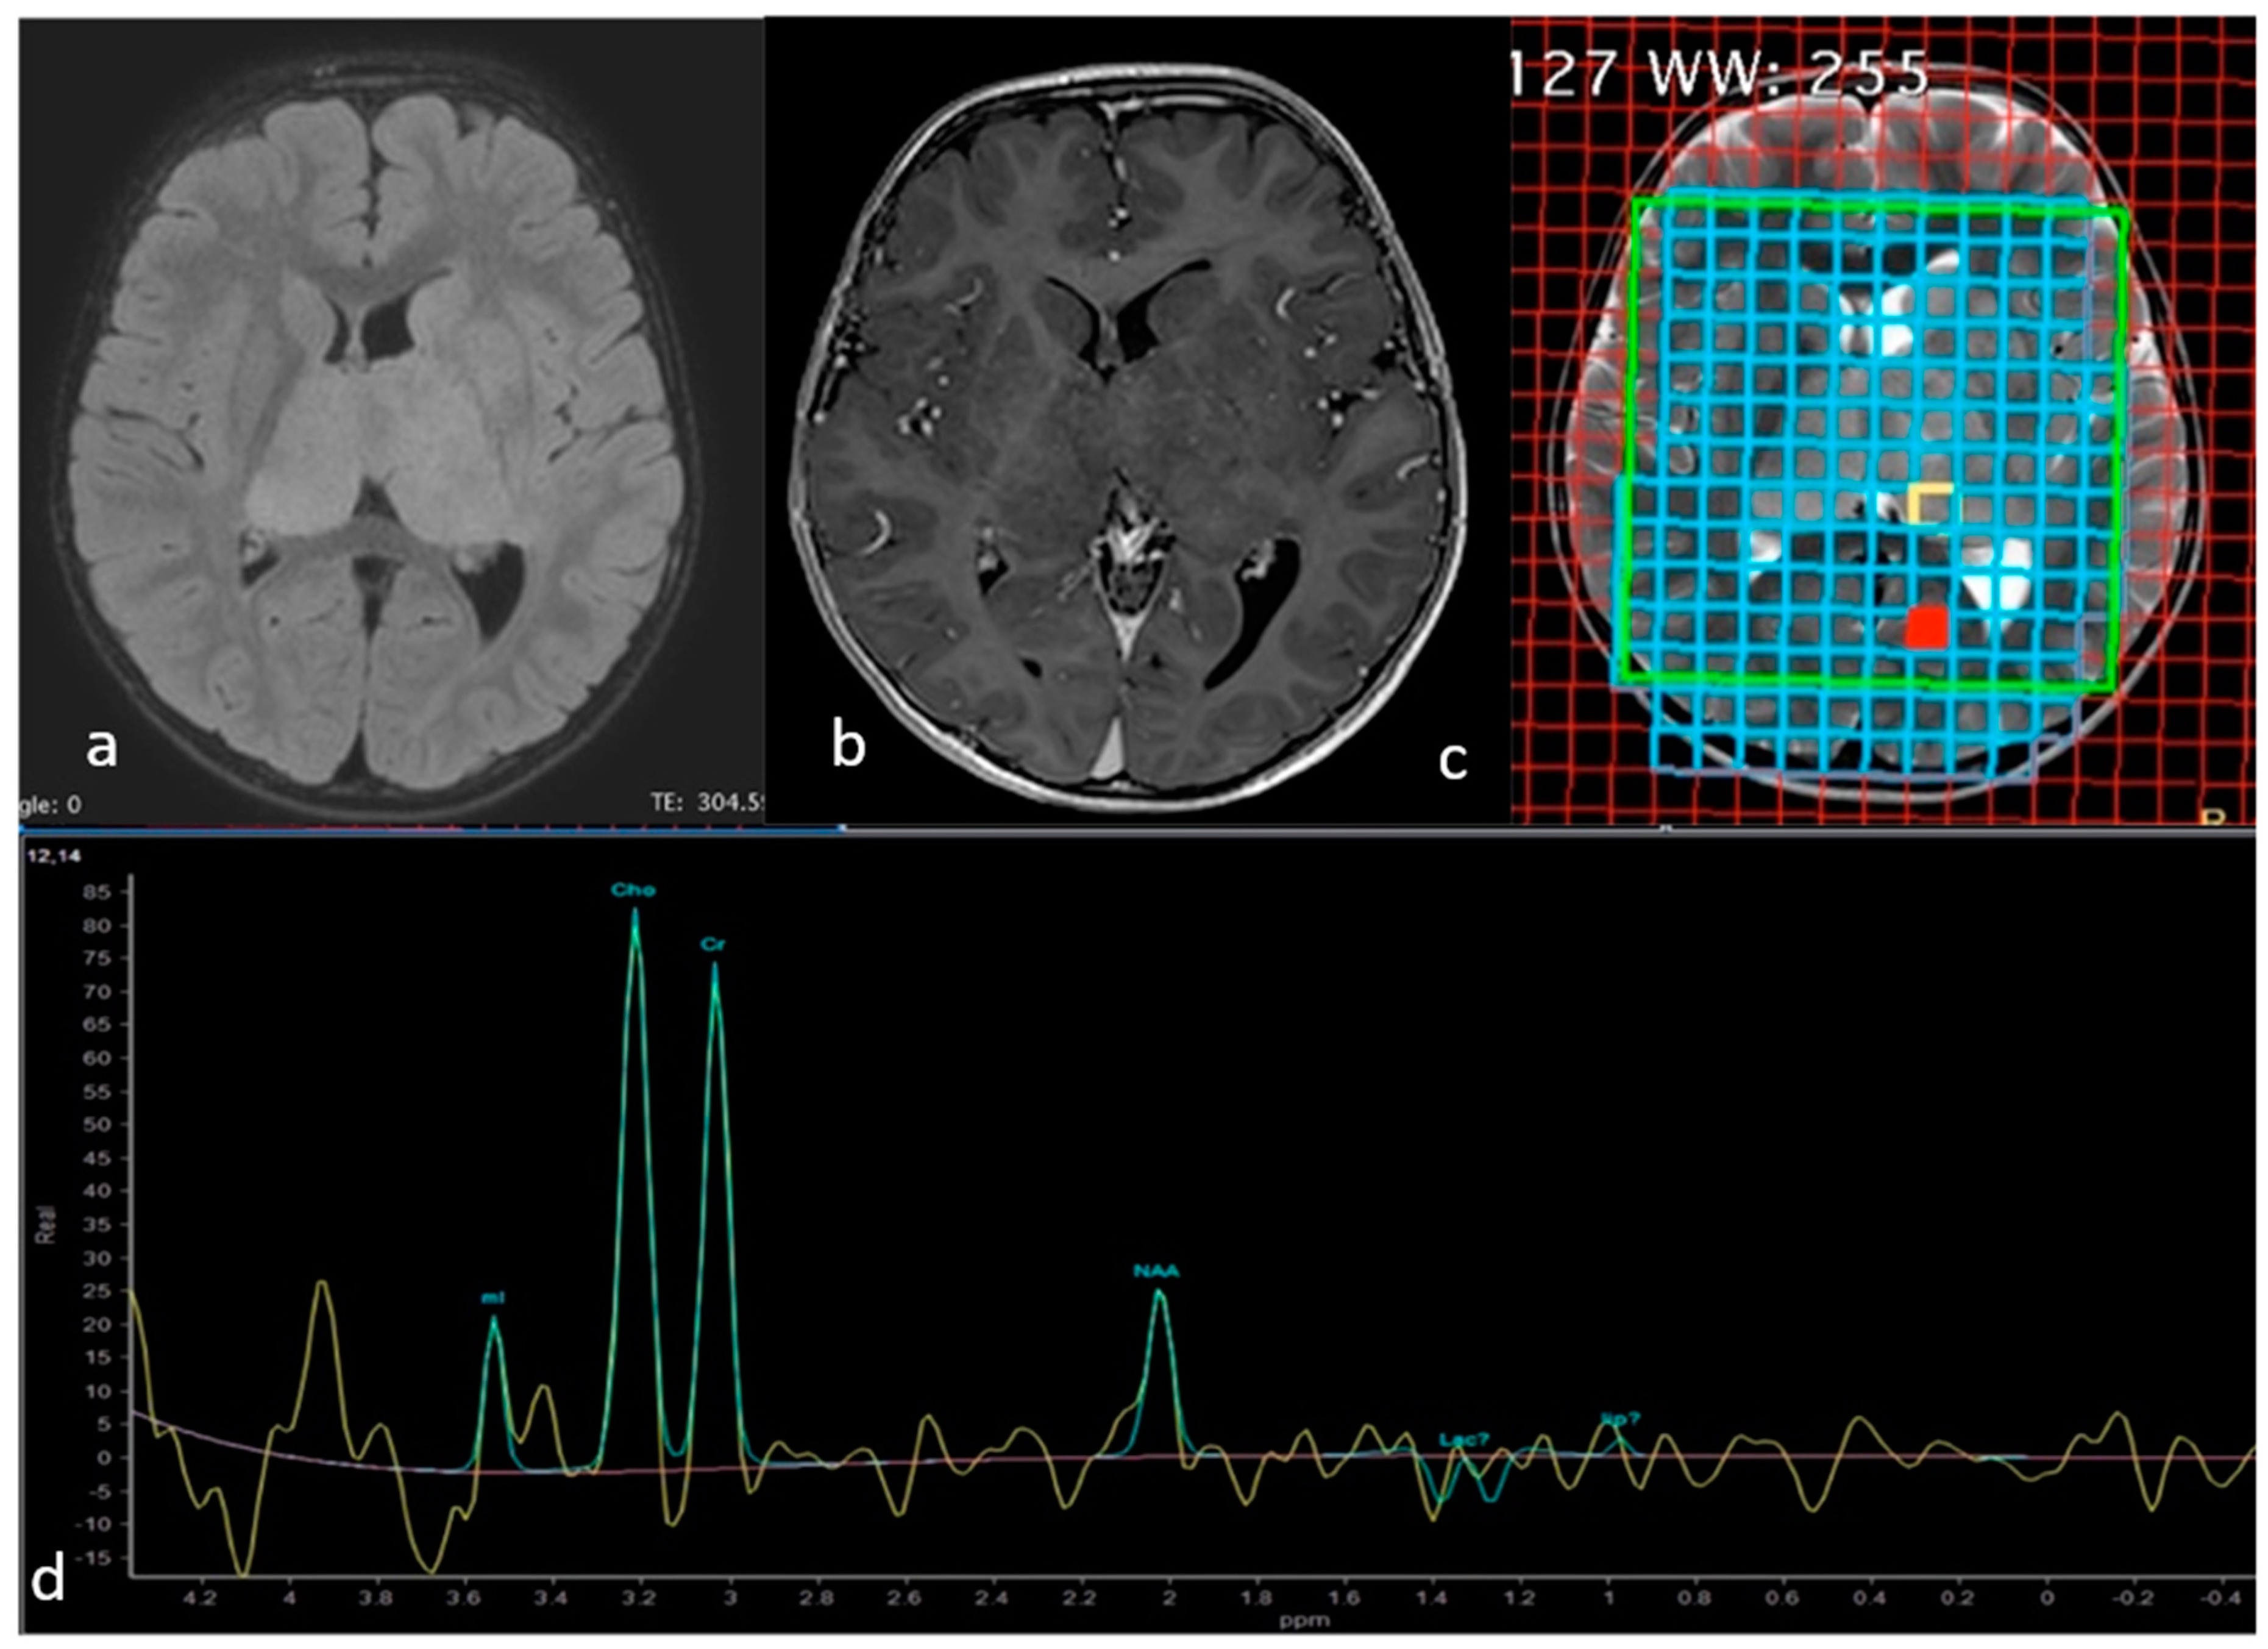

Twenty months later the child started to experience intentional and resting tremor affecting mainly the upper right limb. A brain and spinal MRI showed a bithalamic bicaudate signal abnormality suggestive of malignancy (Figure 2a,b). Multidisciplinary team discussion recommended surgical biopsy in order to obtain histological and immunohistochemical subtyping. The stereotactic biopsy target was identified on the MRI spectroscopy at the level of the inferior portion of the left thalamus, as this was the site of choline peak with low M-acetylaspartate level, expected to have greater tumor activity (Figure 2c,d).

Figure 2.

Axial FLAIR (a), Gadolinium-enhanced T1-weighted (b) and T2-weighted (c) MR images showing the lesion involving both thalami and head of caudate nuclei with no evident contrast enhancement. The spectrum (d) at the level of the yellow square in the left pulvinar corresponded to the area of highest cholin peak, where NAA was markedly decreased, chosen as the biopsy target.